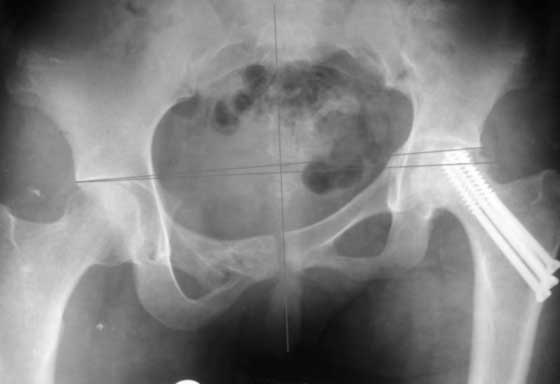

Согласен с Рунковым. Девочка молодая. Имеется ассиметричное расположение вертлужных впадин в прямой проекции. Так как повреждение таза было вертикально-нестабильное, вероятно имеется так же ассиметрия в передне-заднем направлении. Конечно протезом можно компенсировать имеющееся укорочение, но ассиметрично расположенные тазобедренные суставы приведут к нарушению двигательного стереотипа, нарушение походки, остеохондроз и т.д.

До сих пор идут большие дискуссии по поводу высокого центра ротации и единого мнения, насколько я знаю, нет. Компенсация длины, рычагов ягодичных мышц и т.д., а уж при вертикальном смещении таза,влияние его на последующее эндопротезирование просто не узнать (слишком мало наблюдений и много факторов, влияющих на конечный результат). Фото лишний раз подтверждают, укорочение за счет контрактуры.

Привет, Макс. Не торопись, посмотри внимательно на истинную картину. Толстая стрелка указывает на нижний край смещенного кп сочленения.

разговоров нет, смещение значимое, какое оно было, такое и осталось. Будут проблемы и с сидением и с осанкой и т.д. Идеальным вариантом было бы, конечно, исправить деформацию, а потом запротезировать. Но... цена вопроса. сейчас деформация, судя по костной мозоли, стабильная, и таз несет основную свою функцию - опорную, явно КПС не болит. Превратить стабильную деформацию в нестабильную и потом ее исправить - задача непростая, но выполнимая. Оперативное лечение будет сложное, скорее всего многоэтапное и длительное. С определенными рисками, общехирургическими и специфическими, например несращение зоны остеотомий - нестабильный таз, ризидуальное смещение (в пределах 1 см вполне вероятно). Если считать, что на тазе укорочение см 3, остальные 5. все-таки сгибательно-приводящая контрактура. На протезе от контрактуры можно избавиться, да и см 2 удлинить за счет опила, головки. В такой ситуации решение должна принять пациентка и оно должно быть действительно информированным.